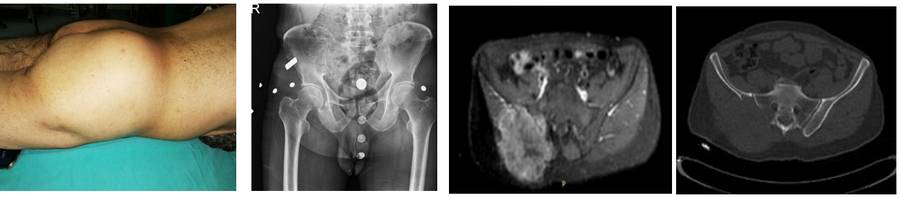

Before the surgery: Clinically, swelling is observed, X-rays show lysis, and MRI and CT scans reveal the presence of metastases, predominantly in the posterior pelvis, causing significant destruction, affecting the sacrum, and accompanied by a large tumor tissue.